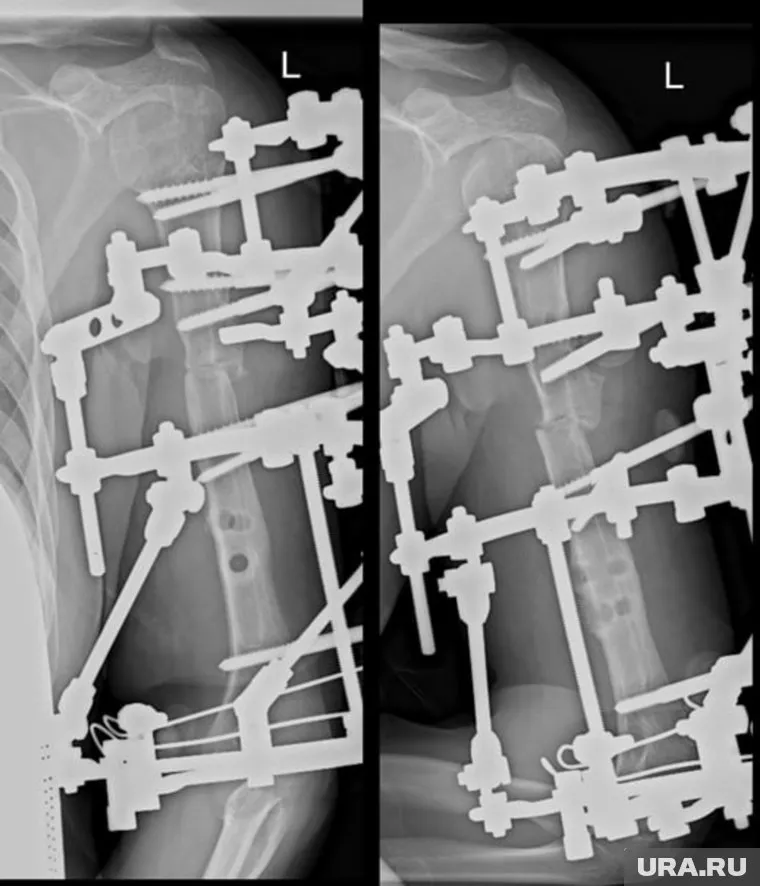

«37-летняя жительница Ставропольского края два года назад упала с высоты восьмого этажа, получила тяжелую сочетанную травму плечевой кости. По месту жительства молодой женщине была сделана операция с использованием интрамедуллярного остеосинтеза», — пишет ведомство. Однако добиться сращения костей не удалось — развился стойкий ложный сустав, а деформация плеча усиливалась. Врачи Центра Илизарова провели комплексное хирургическое лечение: удалили старую металлоконструкцию, устранили деформацию, выполнили остеотомию и локальный остеосинтез с применением аппарата Илизарова.

После операции состояние пациентки стабилизировалось, болевой синдром был устранен, а поврежденная конечность получила надежную фиксацию. На период дальнейшей фиксации в аппарате Илизарова женщина была выписана домой для амбулаторного лечения. За процессом восстановления будут наблюдать дистанционно: врачи центра регулярно анализируют рентгенограммы, присылаемые пациенткой, и контролируют динамику сращения кости.

Фото: tg-канал НМИЦ ТО имени академика Г.А. Илизарова Минздрава России